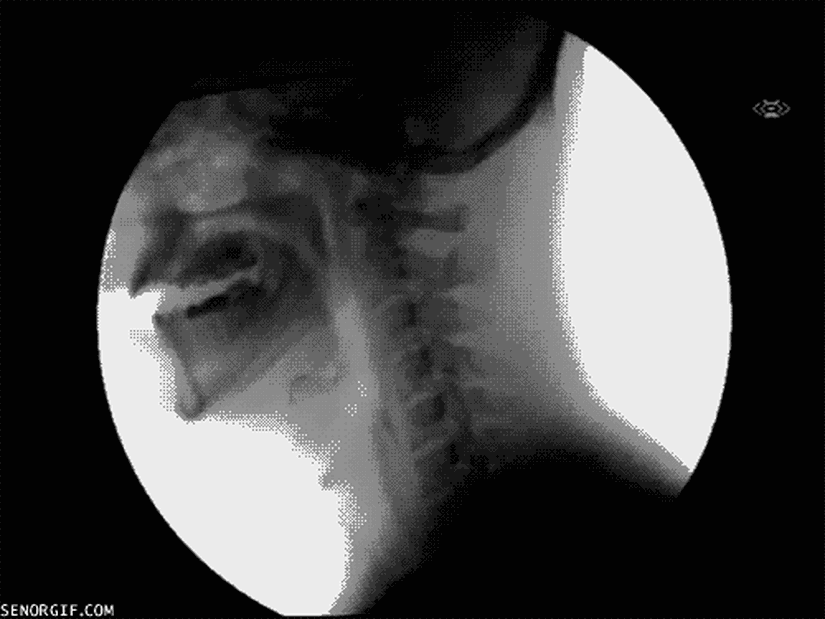

8. Yuttuğumuz sıvıların hareketi...